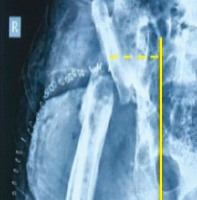

Under tourniquet, through a dorsal midline approach, en bloc resection of the lobulated mass followed by extended curettage of surrounding tumor tissue was performed (Fig. 2), including removal of soft-tissue components between dorsal extensor compartments and careful protection of the flexor sheath and Median nerve volarly.

Figure 2: Intra-operative clinical image depicting the main lobulated mass being excised (top left); intra-operative clinical image after en bloc excision, iliac crest bone grafting, and stabilization with four K-wires. (top right); immediate post-operative antero-posterior radiograph of the wrist (bottom left); histopathological photomicrograph depicting the pathological spindle-shaped stromal cells and multi-nucleated giant cells (bottom right).

Residual cavity margins were curetted to punctate bleeding and burred, followed by application of 2 × 1-min cycles of hydrogen peroxide, while protecting surrounding soft tissues with moist gauze. A structural tricortical iliac crest autograft was fashioned to restore the distal carpal row and achieve normal carpal height, and a morselized cancellous bone graft was packed after debriding the distal cartilaginous surfaces of the proximal carpal bones to permit graft integration. Stable fixation was achieved with two smooth K-wires from the radius and ulna in a criss-cross fashion across the reconstructed column and attaining strong cortical purchase in the metacarpal shafts, one K-wire in retrograde direction from the 2nd metacarpal to the ulna, and one K-wire in retrograde direction from the 4th metacarpal base across the graft to the scaphoid (Fig. 2).